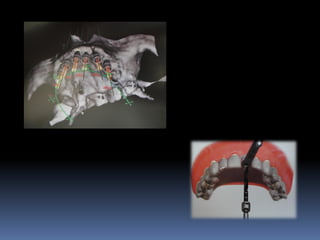

Exames Imaginológicos

Radiografias periapicais, telerradiografias e

panorâmicas;

Tomografias computadorizadas

Softwares de imagens 3D

Guias em Implantodontia

Planejamento protético-cirúrgico

•Guia diagnóstico

•Guia estético

•Guia radiográfico

•Guia cirúrgico

•Guia funcional

Guia radiográfico

-posição ótima do implante com marcadores

radiopacos

•Guta percha

•Esferas e tubos metálicos

•Fios e lâminas metálicas

•Lâmina chumbo do RX

•Dentes de sulfato de bário

•Facilita perfuração, paralelismo e distribuição dos

implantes

•Elimina a medição entre implantes

•Permite alternar as possibilidades de instalação

•Vácuo- press ou própria prótese do paciente

duplicada com acrílico transparente